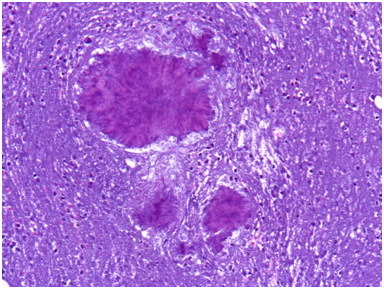

It was performed fine-needle aspiration puncture (FNA) in the subcutaneous nodule of the left knee and right elbow. It was obtained an hemato-purulent liquid without foul odor. A day later, oozing skin fistula appeared in his right knee. Histopathological examination of pus of knee and elbow subcutaneous nodules showed, abundant inflammatory infiltrate with eosinophil and polymorfonuclear neutrophils, and eosinophilic filamentous accumulation suggestive of Actinomyces (Figure 1). No neoplastic cells were obtained. Taking into consideration the results, treatment was switched to intravenous Penicillin G (5million units/6hours). Pus samples of subcutaneous nodules were incubated in anaerobic conditions in chocolate blood agar media. Cultures were positive at tenth day, filamentous Gram-positive fungal-like pathogens (Figure 2). Identifying species of Actinomyces meyeri was made by matrix-assisted laser desorption ionization time-of-flight (MALDI-TOF). It was sensitive to amoxicillin, penicillin, clindamycin, piperacillin-tazobactam and meropenem, and resistent to metronidazole.

Figure 2 Filamentous Gram-positive fungal-like pathogens.

When there is a mucosal barrier disruption, microorganism invades the soft tissues without respecting anatomical plans.11 Hematogenous dissemination can occur from the common primary sites and is reported in 3% of cases.17 Lymphatic spread is uncommon.2,12,14,17 Typical microscopic findings include necrosis with yellowish sulfur granules and filamentous Gram-positive fungal-like pathogens.7 Sulfur granules is seen only in 25% cases.5 Usually, histological study is more sensitive than culture.7 Cultures are negative in more than 50% of cases.7 It is explained because of previous antibiotic therapy, inhibition of Actinomyces spp growth by concomitant microorganisms, inadequate culture conditions, inadequate-short-term incubation, or overgrowth by bystander organisms.7,13,18 The growth usually appears within 5 to 7days, but primary isolation may take up to 2 to 4weeks.17